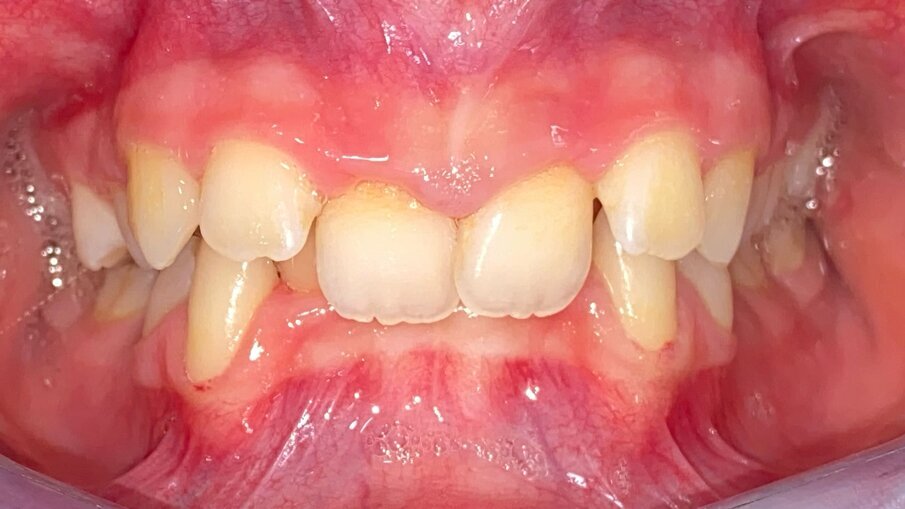

All’esame obiettivo intraorale si riscontra sul piano frontale un severo morso profondo con precontatto traumatico degli incisivi superiori contro la papilla retroincisiva e le rughe palatine anteriori durante la massima intercuspidazione, con overbite di 10 mm (Fig. 5). Dalle foto laterali si evidenzia una malocclusione di Classe II divisione 2 con scissor bite dell’elemento 1.5 (Figg. 6, 7), mentre dalle foto occlusali si rileva un grave affollamento con contrazione di entrambe le arcate maggiore nella zona premolare (Figg. 8, 9). L’analisi di Bolton mostra un eccesso superiore 3-3 di 2,34 mm (73,6%) e 6-6 di 2,76 mm (88,8%). L’analisi cefalometrica evidenzia una Classe II scheletrica, modello facciale normodivergente, angolo interincisale aumentato, incisivi superiori e inferiori retroinclinati (Fig. 10). La radiografia panoramica mostra la presenza dei germi dei terzi molari, assenza di parallelismo tra le radici dei premolari inferiori (Fig. 11) e una sovraeruzione degli incisivi inferiori che crea un doppio piano tra gli incisivi e i molari, segno di una curva di Spee molto profonda.

Fig. 5_Frontale pre-trattamento.